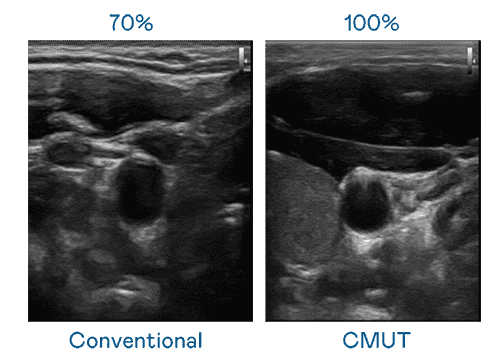

CMUT 技术是一种用电容式微机电元件来产生超音波讯号的技术。。与传统 PZT 压电式技术相比,,,,CMUT 频宽增加 30%,,,更宽频的超音波讯号让影像解析度大幅提升,,,,是实现高影像品质医疗超音波扫描、、、、促进精准医疗发展的关键技术。。。。

大频宽带来超清晰影像

超音波影像的解析度高低,,首先取决于探头能发出的讯号频宽。。。CG电子 CMUT 可提供高清晰的超音波讯号,,,提供高频宽、、高灵敏度、、影像纹理细节更高的超音波影像,,,协助医护人员缩短影像判读时间及利用精准的医疗影像进行诊断。。。。